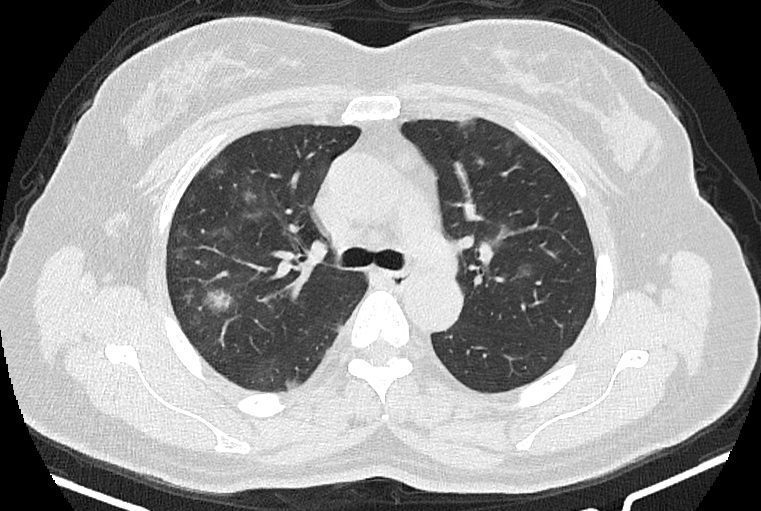

در HRCT از ريه ها(اسپيرال ، مولتي ديتکتور 16، مقاطع اگزيال با ضخامت 1mm بدون فاصله ) ، بدون كنتراست تزريقي :

-Ground glass opacities Patchy پراکنده در ريه ها مشهود است که مطرح کننده Viral pneumonia مي باشد . ( با درگيري 20 درصد حجم ريه )

نتیجه : Highly suggestive of COVID-19